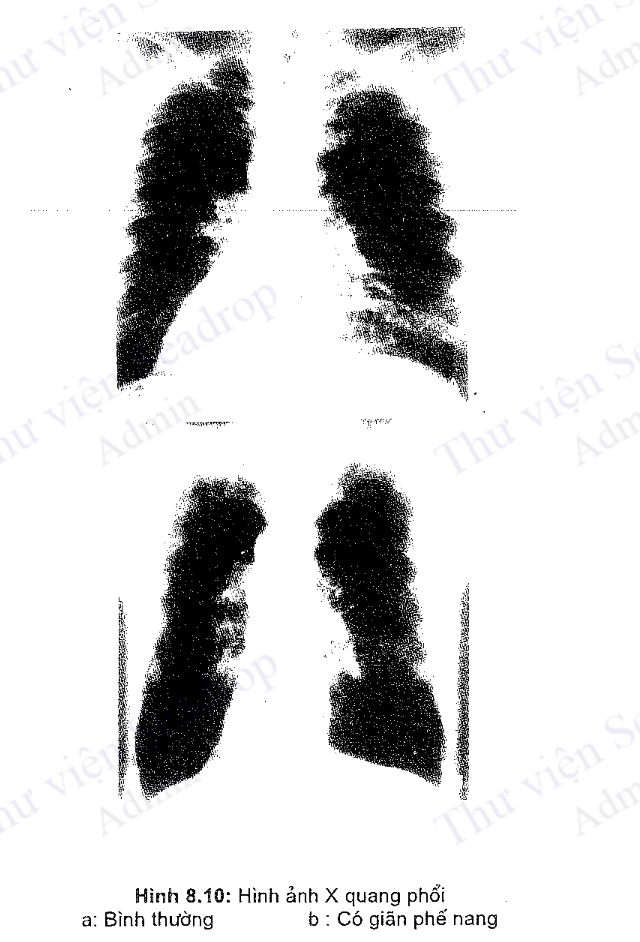

Hình ảnh X quang phổi

Đối với BPTNMT, X quang phổi ít có giá trị trong chẩn đoán. Giai đoạn đầu thường không có dấu hiệu gì đặc biệt. Khi bệnh kéo dài có thể thấy một số hội chứng sau đây:

- Hội chứng phế quản: Dầy thành phế quản, hình đường ray, mạng lưới mạch máu ở phổi tăng đậm tạo thành hình ảnh "phổi bẩn".

- Hội chứng khí phế thũng (giãn phế nang): Phổi hình thùng, tăng sáng, các khoang liên sườn bị giãn rộng, xương sườn nằm ngang, vòm hoành bị đẩy xuống, diện tim bị nhỏ lại (mỏm tim lệch ra phía sau (hình 8.10).

- Trên phim phổi chuẩn có thể dựa vào một số chỉ số sau đây nghĩ đến phổi bị giãn phế nang: phim phổi thẳng chiều cao của phổi lớn hơn 30cm, trên phim nghiêng vòm hoành thấp hơn xương sườn 7 ở phía trước, góc ức hoành lớn hơn 90°.

- Hội chứng mạch máu: Mạch máu ở trung tâm to, nhưng ở ngoại vi thì thưa thớt.